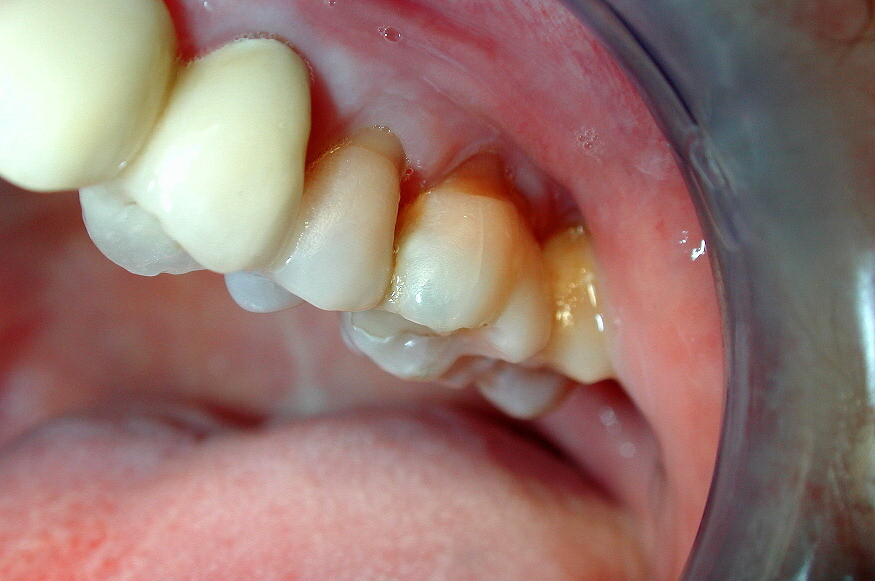

Root resorption in adult teeth is usually a result of some sort of trauma to the teeth, often caused by forced shifting of the teeth. This can happen after someone suffers a blow to that tooth, such as in a high-impact sport, but it can also happen as a result of orthodontic treatment.

When we wear braces, the teeth are being pushed and pulled into alignment to produce a healthier bite. Ideally, the bone should be remodeled to accommodate the new position of the teeth, but if the shift happens too quickly, the bone might not have time to readjust, leaving the roots of the teeth to decay and be absorbed back into the rest of the body. If the roots dissolve too much, they could loosen in the gums and even fall out.

In addition to the possibility that the teeth were moved too quickly in the process of orthodontic treatment, other possible factors include the duration of the orthodontic treatment, the amount of force exerted on the teeth, and the direction in which the teeth were moved.